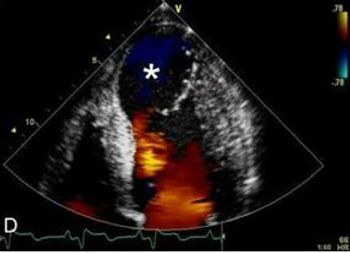

Primary care physicians play a central role in preventing and managing cardiovascular disease. Take a look at the variety of presentations in this week's photo quiz to test your knowledge.